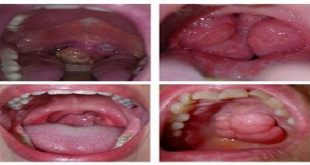

Tổn thương hồng sản (mảng đỏ), nguy cơ hóa ác cao.

Ung thư bờ lưỡi phải.

Ung thư nướu (lợi) răng hàm dưới bên trái.